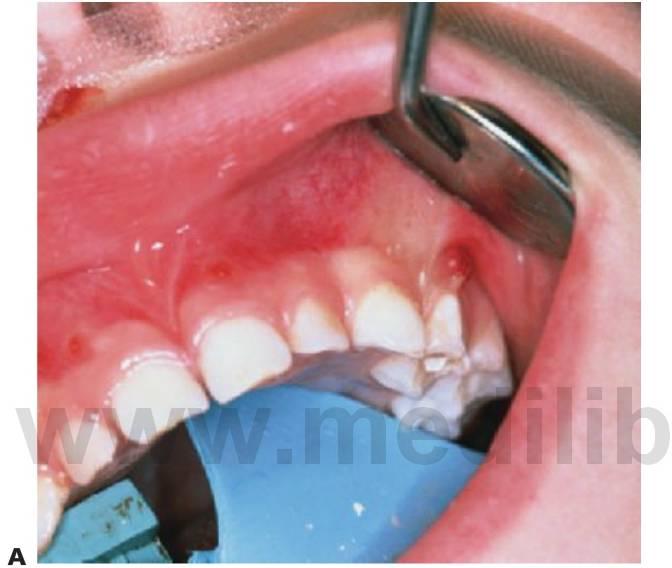

- Varios dientes ausentes (fig. 9.1 B).

Los dientes son pequeños y cónicos y a menudo presentan un gran diastema anterior (fig. 9.3). Sus manifestaciones pueden limitarse a un solo diente ausente o a un incisivo lateral en clavija (v. hipótesis de Lyon, más adelante) y las mujeres heterocigóticas suelen ser diagnosticadas gracias a este tipo de dentición.

Tratamiento

El objetivo del tratamiento es proporcionar una función adecuada, mantener la dimensión vertical y restaurar el aspecto estético. La mejor opción desde el punto de vista de las consideraciones sociales es el inicio del tratamiento a los 2-3 años de edad. Sucede a menudo que los padres pretendan con ahínco «normalizar» el aspecto del niño. Un primer paso suele ser la colocación de restauraciones de composite para enmascarar el aspecto «similar a un colmillo» del diente anterior caniniforme (fig. 9.3A). Más adelante se efectuará la provisión de prótesis para que sufra menos burlas, sobre todo en el momento en que el niño empieza a ir a la escuela. La prótesis puede prepararse tan pronto como al niño se le puedan tomar impresiones, pero la realidad es que el primer juego de prótesis suele llevarse en el bolsillo y a medida que el niño crece se desarrolla el deseo de tener un aspecto más normal. Gracias a una incentivación y refuerzo positivo del niño, la mayoría de los niños llevarán puestas sus prótesis.

- Reconstrucciones con composite sobre los dientes cónicos grabados con ácido.

- Pueden añadirse también botones de resina composite o botones ortodóncicos adheridos para proporcionar zonas de retención para los ganchos y retenedores de la prótesis (fig. 9.5).